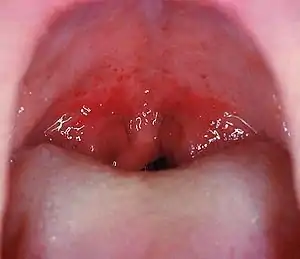

| A culture positive case of streptococcal pharyngitis with typical tonsillar exudate in a 16-year-old. | |

Mouth wide open showing the throat

A throat infection which on culture tested positive for group A streptococcus. Note the large tonsils with white exudate.